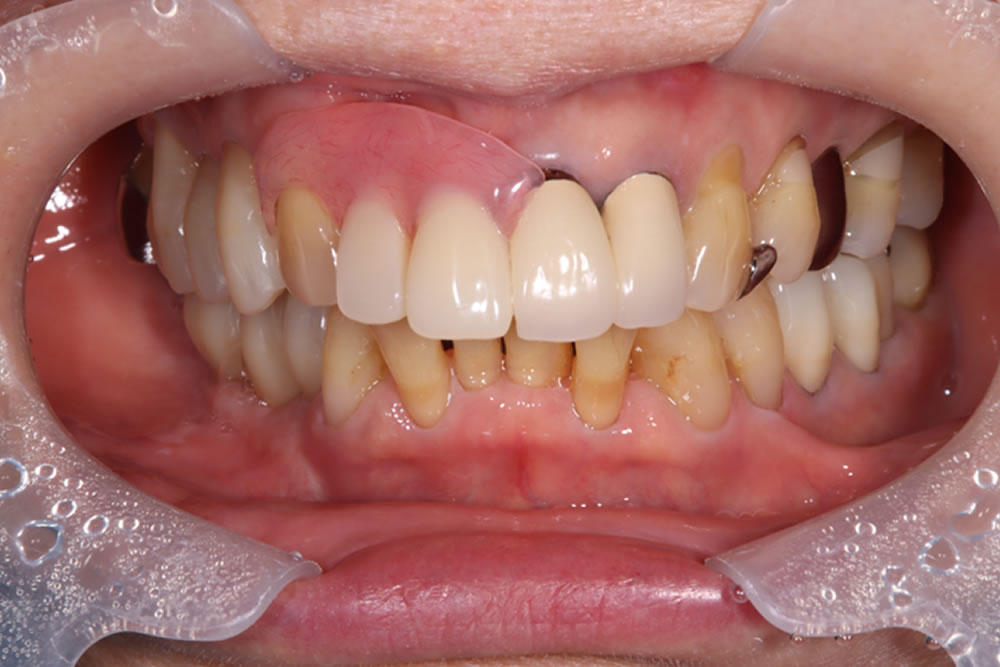

治療前後の比較

インプラント治療により、固いものもしっかり噛めるようになったとのことでした。また、歯肉移植を併用したことで、インプラント周囲の清掃性も向上しました。

| 年齢・性別 | 70代 女性 |

| 治療期間 | 8ヵ月 |

| 治療回数 | 20回 |

| 治療費(税込) | 1,725,000円 |

| リスク・注意点 | 外科処置には術後麻痺等のリスクがあります。 骨の状態によっては治療期間が長くなる場合があります。 |